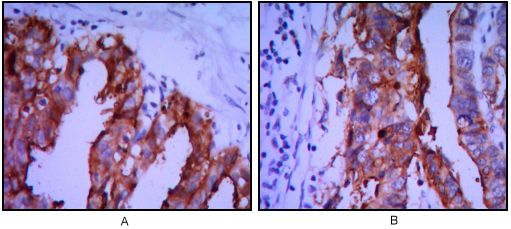

IHC-P analysis of ovarian cancer (A), stomach cancer (B) using GTX82823 Placental Alkaline Phosphatase antibody [3E5].